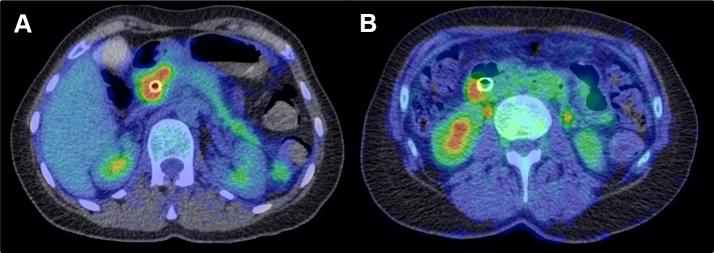

Functional imaging gives information about physiological heterogeneity in tumours. The utility of functional imaging tests in providing predictive and prognostic information after chemoradiotherapy for both oesophageal cancer and pancreatic cancer will be reviewed. The benefit of incorporating functional imaging into radiotherapy planning is also evaluated. In cancers of the upper gastrointestinal tract, the vast majority of functional imaging studies have used (18)F-fluorodeoxyglucose positron emission tomography (FDG-PET). Few studies in locally advanced pancreatic cancer have investigated the utility of functional imaging in risk-stratifying patients or aiding target volume definition. Certain themes from the oesophageal data emerge, including the need for a multiparametric assessment of functional images and the added value of response assessment rather than relying on single time point measures. The sensitivity and specificity of FDG-PET to predict treatment response and survival are not currently high enough to inform treatment decisions. This suggests that a multimodal, multiparametric approach may be required. FDG-PET improves target volume definition in oesophageal cancer by improving the accuracy of tumour length definition and by improving the nodal staging of patients. The ideal functional imaging test would accurately identify patients who are unlikely to achieve a pathological complete response after chemoradiotherapy and would aid the delineation of a biological target volume that could be used for treatment intensification. The current limitations of published studies prevent integrating imaging-derived parameters into decision making on an individual patient basis. These limitations should inform future trial design in oesophageal and pancreatic cancers.

功能成像可提供有关肿瘤生理异质性的信息。本文将综述功能成像检查在食管癌和胰腺癌放化疗后提供预测和预后信息方面的效用。同时也评估将功能成像纳入放疗计划的益处。在上消化道癌症中,绝大多数功能成像研究都使用了(18)F-氟脱氧葡萄糖正电子发射断层扫描(FDG-PET)。在局部晚期胰腺癌中,很少有研究探讨功能成像在对患者进行风险分层或辅助靶区定义方面的效用。从食管癌数据中出现了某些主题,包括对功能图像进行多参数评估的必要性以及反应评估的附加价值,而不是依赖单一时间点的测量。目前,FDG-PET预测治疗反应和生存的敏感性和特异性还不够高,无法为治疗决策提供依据。这表明可能需要一种多模态、多参数的方法。FDG-PET通过提高肿瘤长度定义的准确性和改善患者的淋巴结分期,改善了食管癌的靶区定义。理想的功能成像检查应能准确识别放化疗后不太可能实现病理完全缓解的患者,并有助于勾勒出可用于强化治疗的生物靶区。已发表研究的当前局限性阻碍了将成像衍生参数纳入个体患者的决策制定。这些局限性应为未来食管癌和胰腺癌的试验设计提供参考。